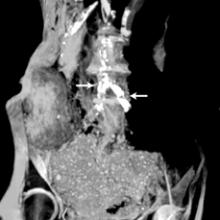

New research published in the June issue of Global Heart, the journal of the World Heart Federation, shows that there are no significant differences in the incidence or severity of atherosclerotic disease (narrowing of the arteries with fatty deposits) between ancient and modern people, proving that atherosclerosis is not just a disease of modern times. The journal included three articles [1,2,3] on the finding of the Horus study, which used computed tomography (CT) scans from ancient mummies to compare arterial calcification caused by Horus atherosclerosis.